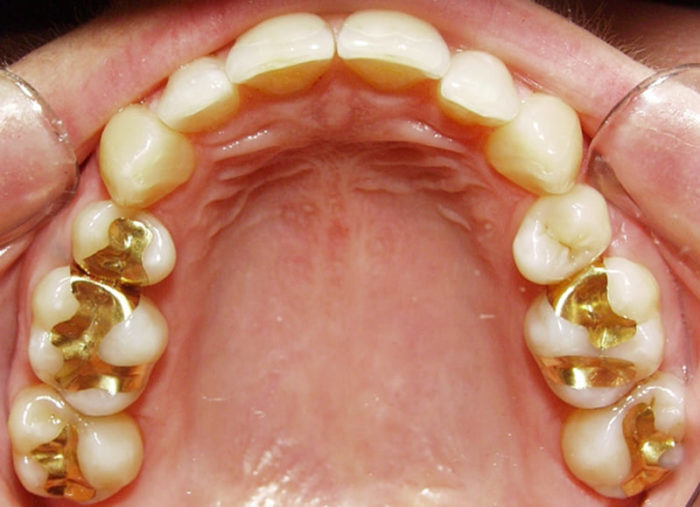

2.1 Trám vàng

2.1.1 – Ưu điểm:

Trám vàng chịu được lực ăn nhai tốt và được nhiều người lựa chọn dùng để trám răng hàm – nơi có lực nhai mạnh trong chức năng răng miệng. Độ bền của trám vàng cao, là kim loại không bị ăn mòn bởi acid, tuổi thọ miếng trám 10 – 15 năm và có thể cao hơn theo khả năng gìn giữ của mỗi người.

2.1.2 – Nhược điểm:

Tính thẩm mỹ không cao do sắc tố vàng nên được ít người ưa chuộng. Giá thành của vàng cao hơn tất cả các vật liệu khác. So sánh với bạc Amalgam thì chi phí cao gấp khoảng 10 lần và cần đến nha khoa khoảng 2 lần 1 tuần để điều trị. Vàng có khả năng dẫn điện nên trong quá trình làm có thể dẫn tới tình trạng sốc điện, tuy nhiên trường hợp này rất hiếm khi xảy ra trong quá trình điều trị.